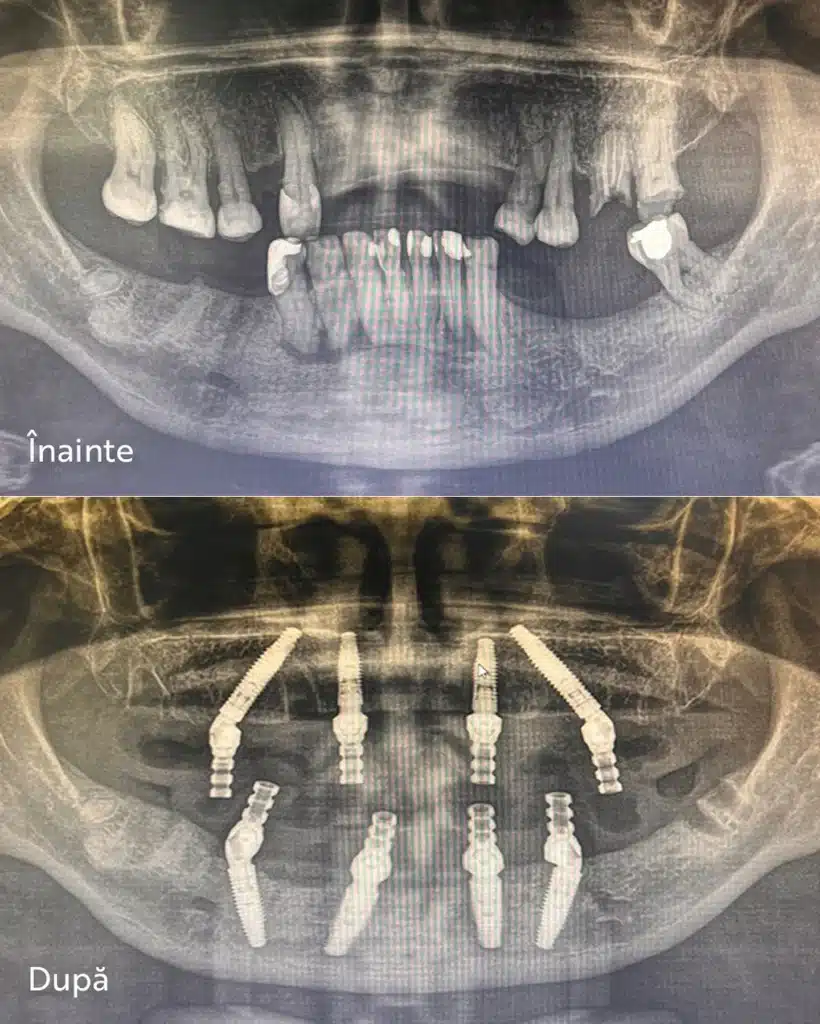

Mai jos prezentăm un caz real de implant dentar All‑on‑4 / All‑on‑6 realizat în clinica MedPrime din Cluj. Radiografiile înainte și după intervenție arată stabilizarea imediată, poziția corectă a implanturilor și reconstrucția completă a arcadelor.

Intervenția All‑on‑4 / All‑on‑6 permite înlocuirea completă a dinților lipsă printr‑un protocol rapid și minim invaziv. Implanturile sunt poziționate strategic pentru a asigura stabilitate ridicată, iar pacienții beneficiază de restaurări imediate și rezultate estetice excelente.

Acest caz a fost realizat la MedPrime Cluj.